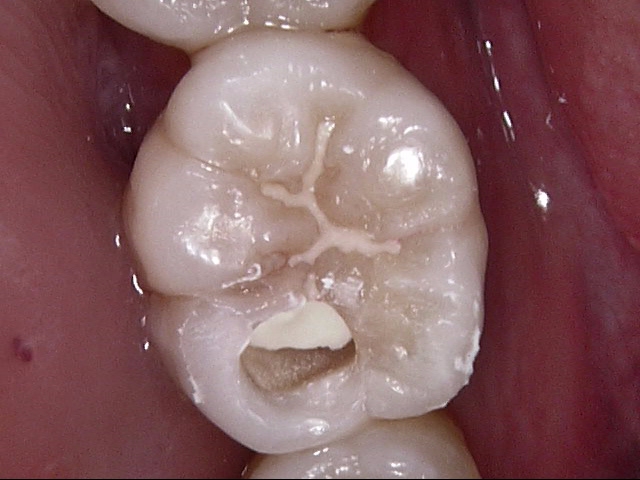

この歯を実際にお口の中で見ると、こういう風に見えます。

解説します。

赤丸の部分の歯ぐきが腫れています。矢印の部分は歯の縦に亀裂が入った様子が見られます。

この歯は大きい奥歯で、根が3本ありますが、そのうちの1本が折れており、他の2本もダメージがかなり大きかったので、無理に残しても数年持つかどうかという状態でした。

患者さんとよく話し合って、抜歯することになりました。